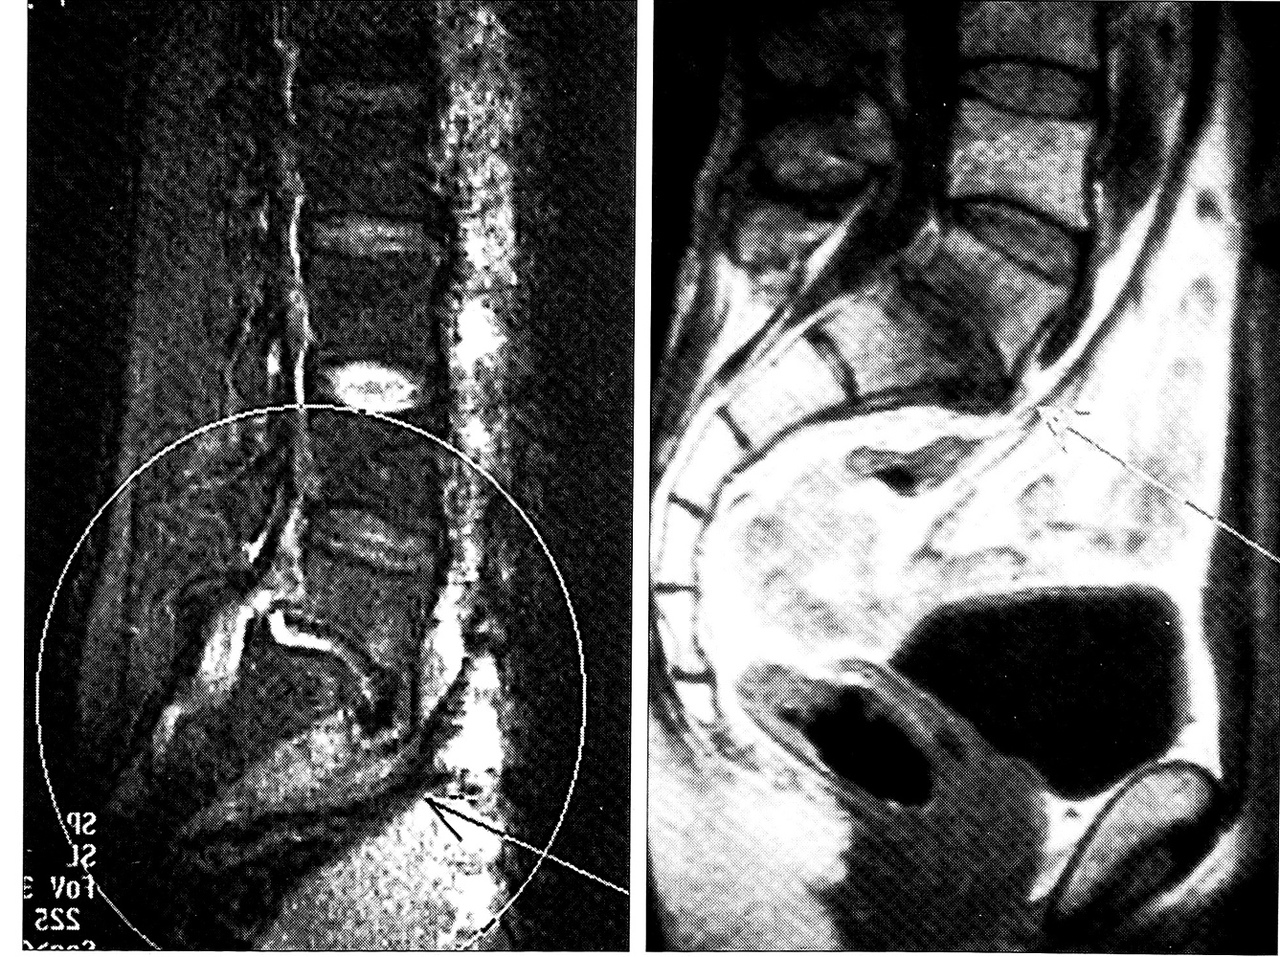

Ортопедический статус: ходит с трудом, отмечает резкие боли в грудном отделе позвоночника. Пальпация и перкуссия остистых отростков ТЗ-5 позвонков резко болезненна, определяется кифотическая деформация. Положительный симптом Томпсона. Неврологический статус: брюшные рефлексы отсутствуют, коленные и ахилловы рефлексы оживлены, нижний парапарез. Анализ крови: НЬ 100 г/л, л. 17,9* 109л, СОЭ 34 мм/ч. МРТ (рис. 3, а): позвонок Тб полностью разрушен, клиновидно деформирован. Замыкательные пластинки разрушены. Внутренняя структура гиперинтенсивна (отек костного мозга). Определяется эпидуральный абсцесс на уровне Т5-6 позвонков с четкими признаками компрессии спинного мозга. Имеются признаки превертебрального абсцесса. На аксиальных срезах картина воспалительного поражения Т4-6 позвонков с деструкцией Т5, эпидуральный абсцесс с компрессией спинного мозга, паравертебральным абсцедированием (вероятнее всего, остеомиелит).

Послеоперационный период без осложнений. Больная выписана в удовлетворительном состоянии в ортопедическом корсете через 1 мес после операции. Обследована через 2 года: жалоб нет, температура тела нормальная, анализы крови в пределах нормы, регресс неврологической симптоматики. Является инвалидом II группы. По данным МРТ — костный блок на уровне Т4-6 позвонков (рис. 3, б).

Рис. 3. МРТ больной И. a — до операции: деструкция тел Т4~6 позвонков, превертебральный абсцесс; б — через 2 года после операции: костный блок Т4-6 позвонков.